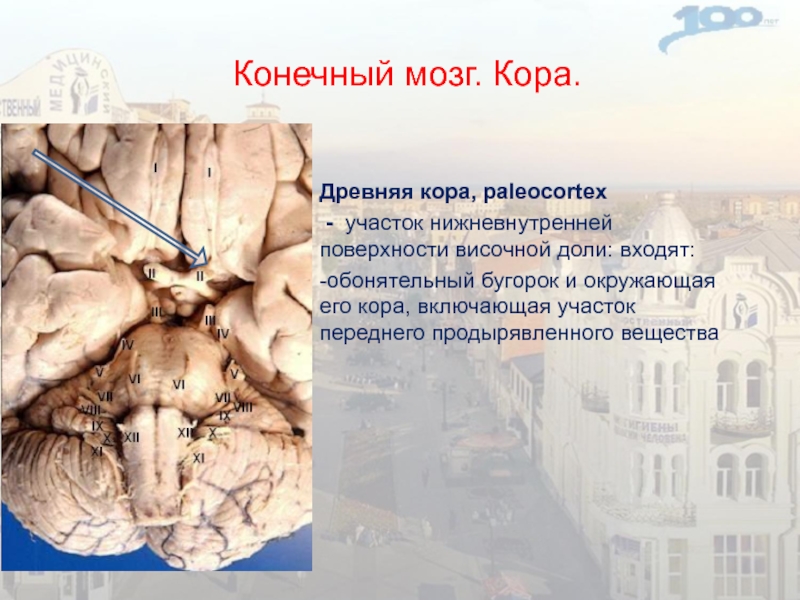

Необычные объекты: Переднее продырявленное вещество

Раздел: Альбом открытий